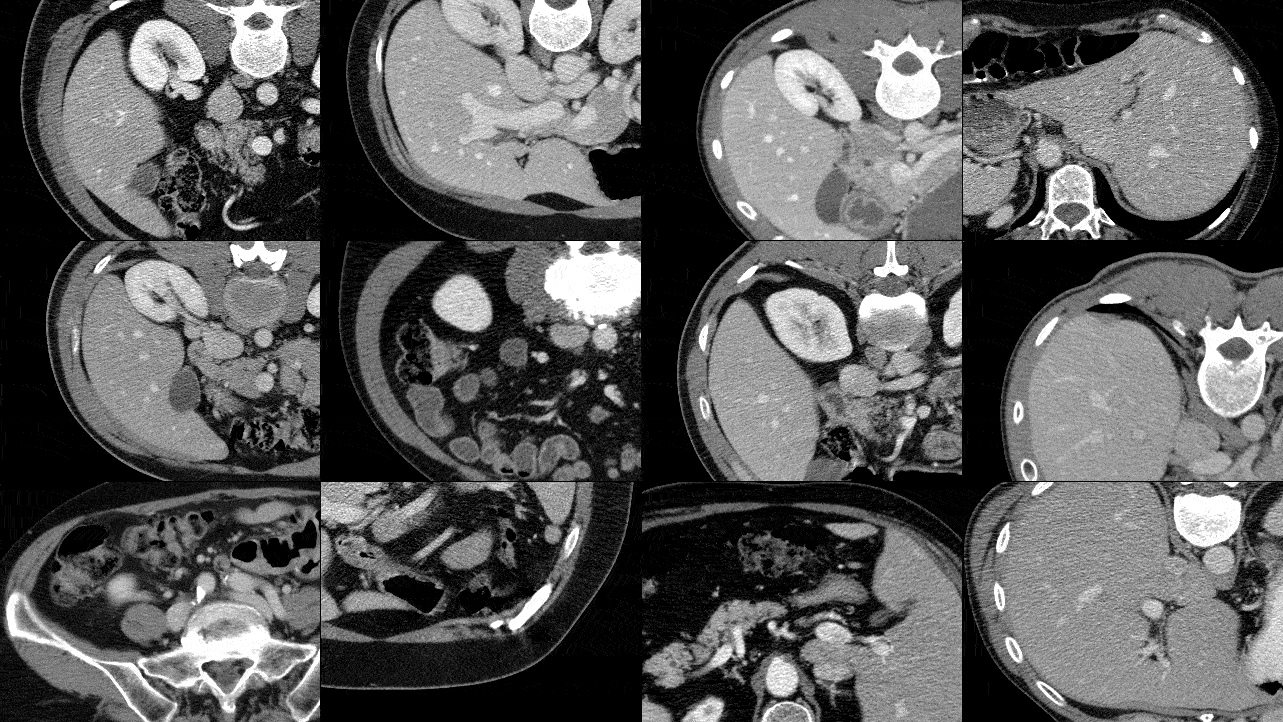

Embracing Medical Data

Embracing Massive Medical Data

Yu-Cheng Chou, Zongwei Zhou, Alan Yuille

MICCAI 2024